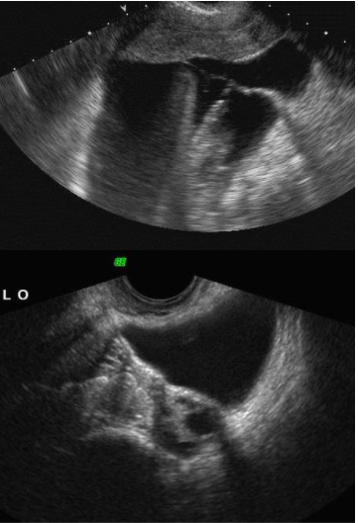

twisted vascular pedicle

image shows a twisted vascular pedicle extending into an enlarged and hypoechoic ovary. a twisted vascular pedicle is detected in about 88% of torsion cases. It is considered the most specific and definitive sign of torsion.

ovarian torsion

The first image demonstrates a normal right ovary. The left ovary is enlarged, midline, does not enhance normally, and demonstrates regions of restricted diffusion, compatible with ovarian torsion. The patient underwent removal of the nonviable left ovary.

most sensitive and specifics signs for ovarian torsion

sensitive sign: enlarged ovary (typically > 25mL)

Specific sign: whirpool sign (twisting of the pedicle)

Additional findings include: